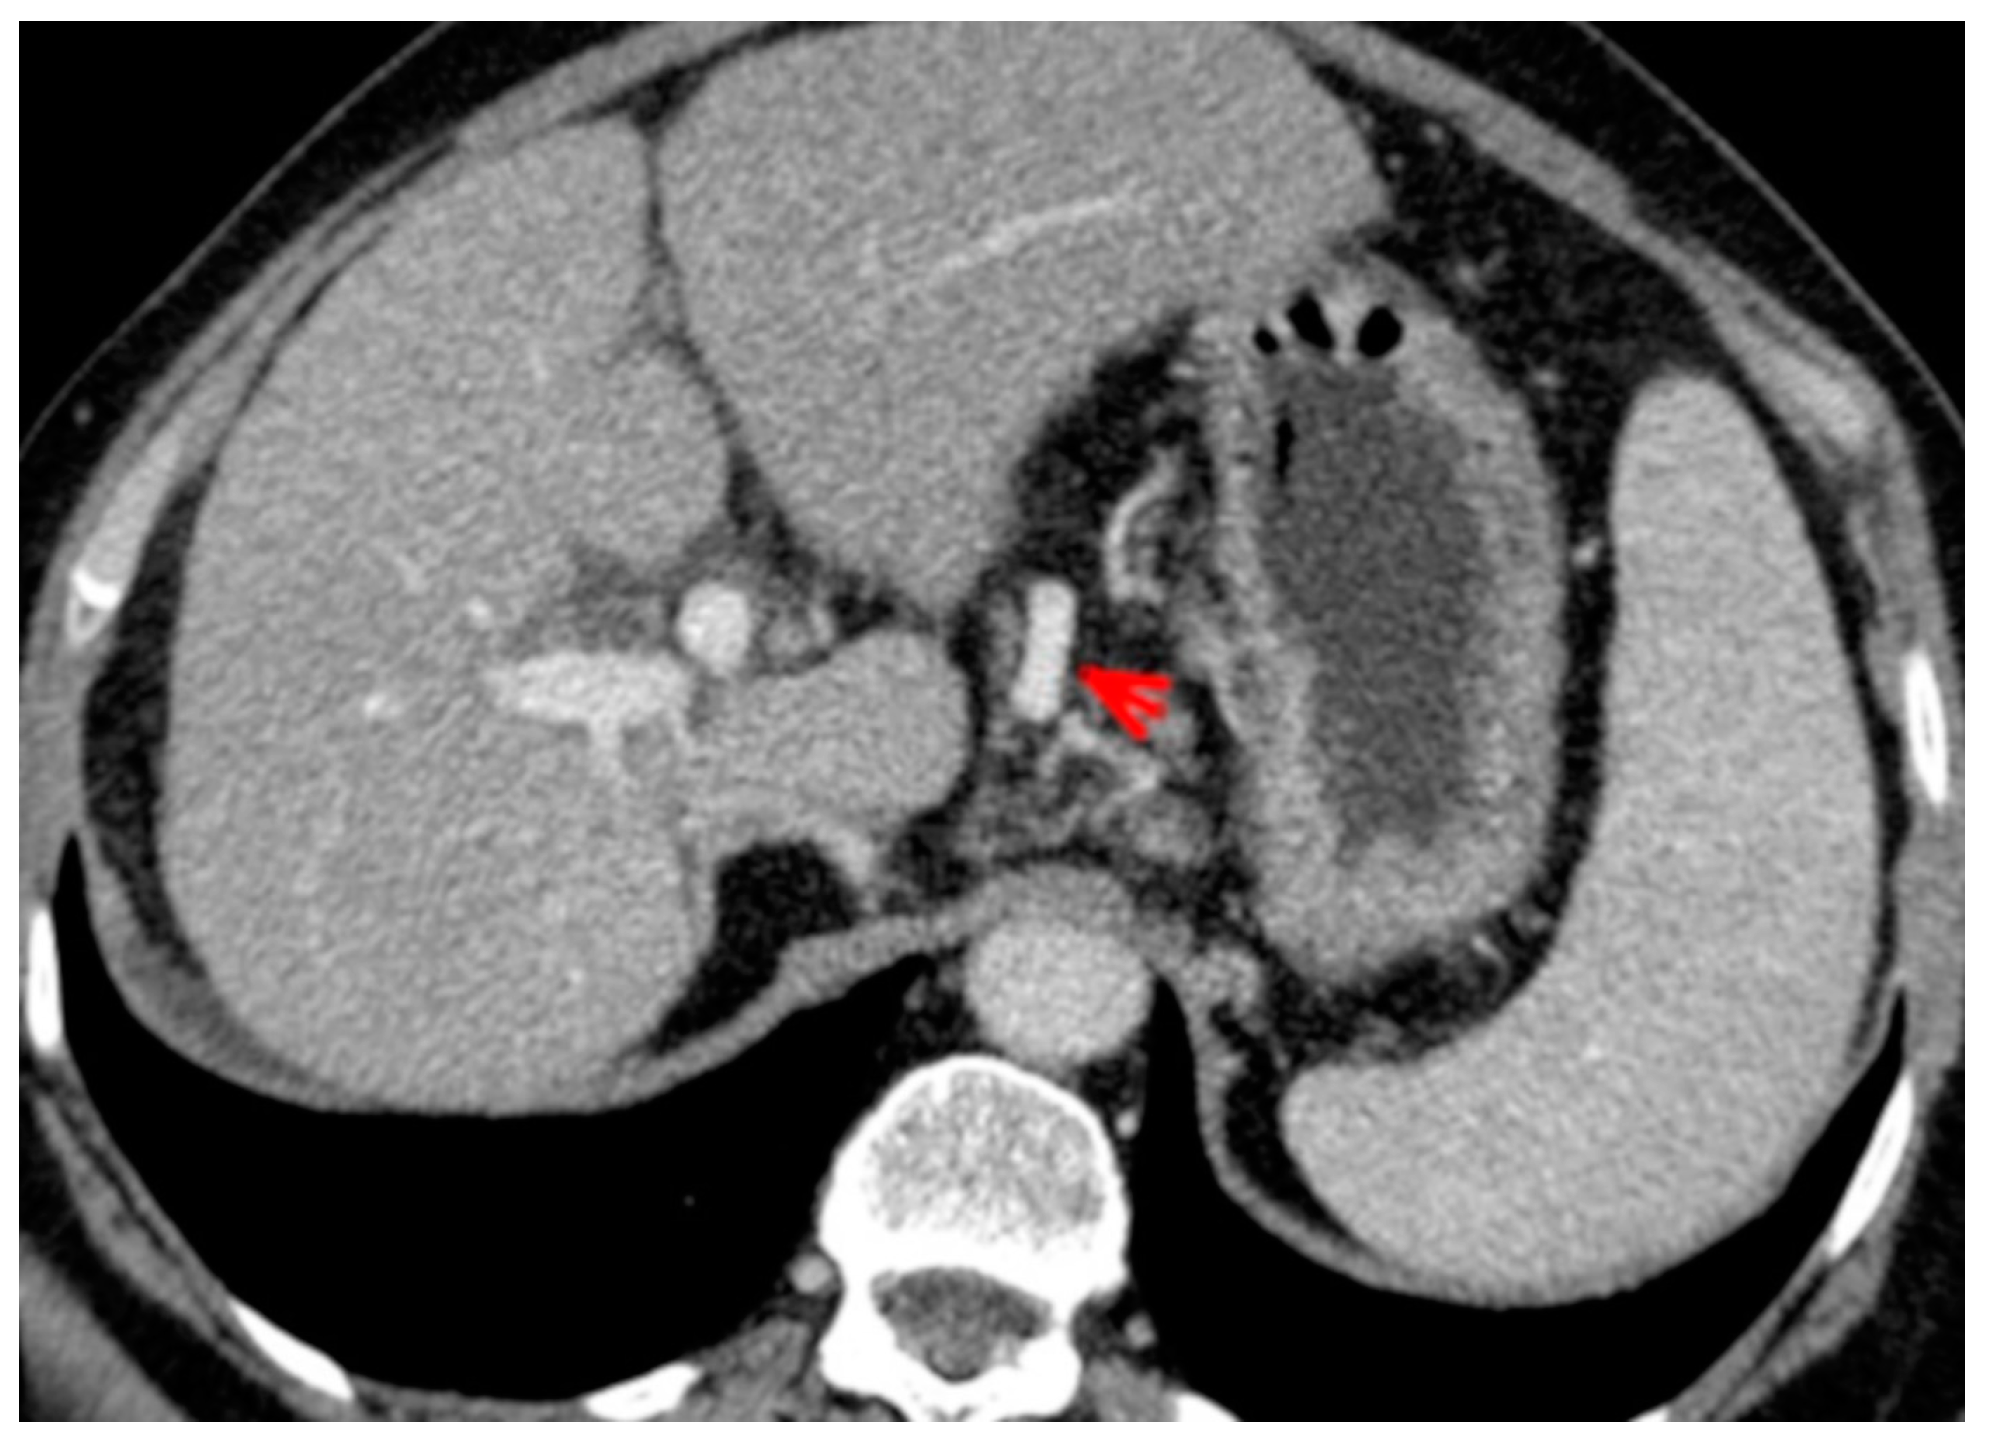

For this study, the images were retrospectively analyzed in consensus by two readers with experience in the field of abdominal imaging. The two readers assessed the following CT features: (1) The presence or absence of paraoesophageal varices and the size(mm) of the largest varix (Figure 1); (2) the presence or absence of paragastric varices and the size (mm) of the largest varix (Figure 2); (3) the largest diameter of the left gastric vein (Figure 3); (4) the presence or absence of splenorenal shunts and the size(mm) of the shunt (Figure 4); (5) the presence or absence of a repermeabilized round ligament and the size(mm) of it (Figure 5).

Figure 3. Axial contrast-enhanced CT shows enlarged left gastric vein (red arrow).